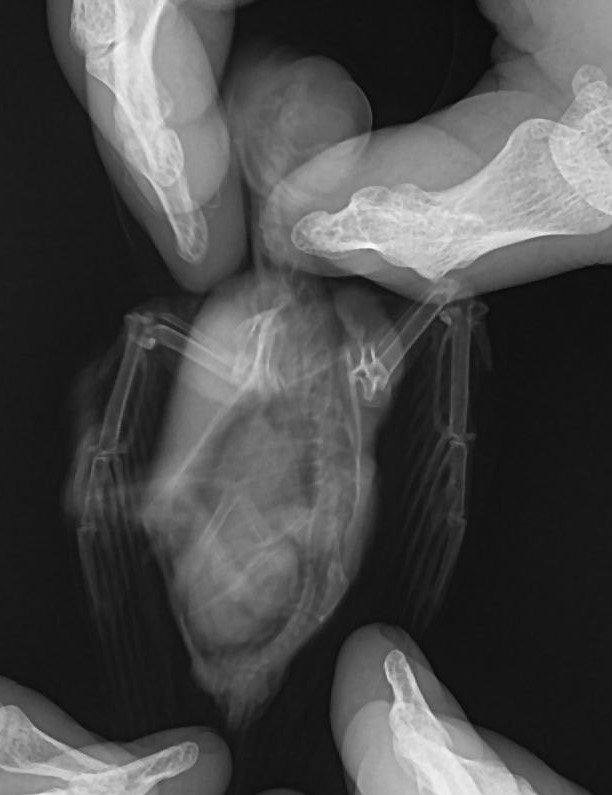

Стриж, открытый перелом крыла, торчит кость

Karpinsky опубликовал тема в Содержание стрижей в домашних условиях

Был найден на тротуаре поздно вечером, чуть ниже локтя кровоточащая рана, кость торчит наружу. При взмахах крылом "кисть" свободно болтается, - видно, что держится только на мягких тканях. Птица паникует, машет крыльями и вопит от ,автоматически этими действиями расковыривает рану. Я прикладывала к ране марлевый тампон, смоченный в дициноне, влила с пальца пару капель воды в клюв, позже на рану положила немного Левомеколя. Подскажите, как ещё помочь птице, тем более "на ночь глядя". Сложно с ней, как бы не умерла от болевого шока прежде, чем я смогу организовать ей толковое лечение. Не лучше ли отрезать болтающуюся часть крыла - всё равно обездвижить его невозможно, да и срастить оторванные части кости вряд ли получится. Чем кормить - ловить мух и комаров и, зажав в пинцете, подносить к клюву? Есть ли какие-то подходящие корма в зоомагазинах? Сколько птица (если выживет) должна съедать в день и как часто? Как лучше поить,чтобы не попасть в дыхательное горло? Надо птицу держать в тепле, или наоборот, в прохладе, чтобы кровотечение не возобновлялось? Заранее спасибо.- 3 ответа